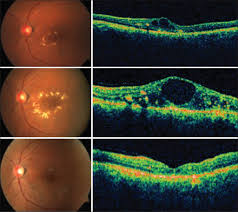

1. Age related macular degeneration : (ARMD)

This is degeneration of central part of retina due to age (more than 60 years). Patient has painless decrease of vision. Advanced cases have rupture of blood vessels in the lesion and require laser treatment or intravitreal injections of anti VEGF agents.

There are two types of AMD: dry (atrophic) and wet (neovascular or exudative). Most AMD starts as the dry type and in 10-20% of individuals, it progresses to the wet type.

Dry ARMD;In dry age-related macular degeneration, small white or yellowish deposits, called drusen, form on the retina, beneath the macula, causing it to deteriorate or degenerate over time.

Wet ARMD;In wet age-related macular degeneration, abnormal blood vessels under the retina begin to grow toward the macula. Because these new blood vessels are abnormal, they tend to break, bleed, and leak fluid, damaging the macula and causing it to lift up and pull away from its base. This can result in a rapid and severe loss of central vision.

Dry ARMD

wet ARMD

wet ARMD advanced